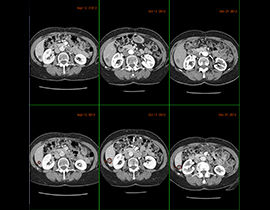

Erweiterte Visualisierung für CT